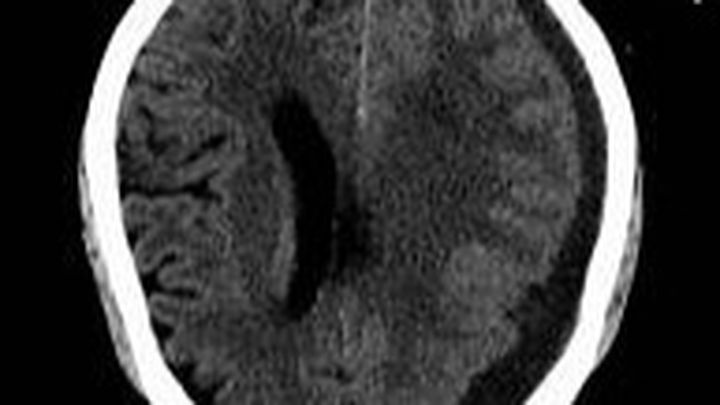

Chronic Subdural Hematoma is a serious medical condition in which blood accumulates between the brain's surface and its outermost covering. This condition often results from head injuries, and it can lead to severe headaches, cognitive impairments, and even life-threatening complications. Abid's condition has unfortunately progressed to a critical stage, making it difficult for him to carry out even the simplest daily activities.